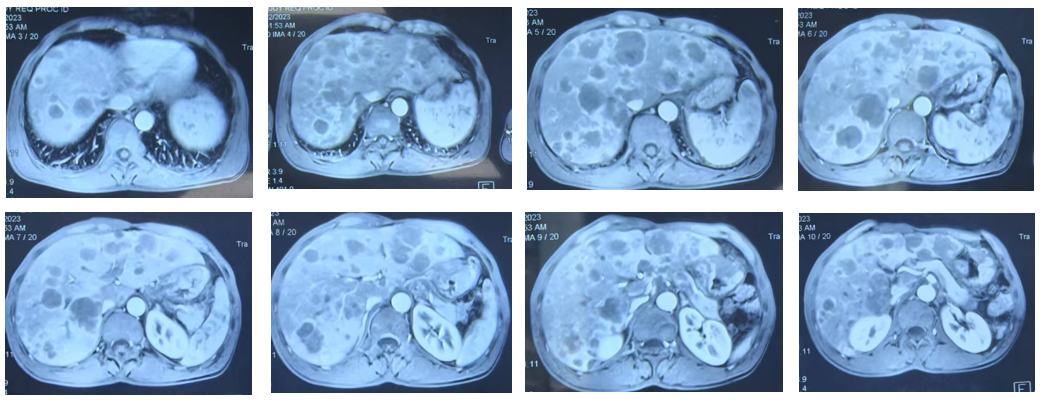

腹部MRI提示肝脏多发、弥漫性转移瘤,肿瘤负荷巨大(图1)。